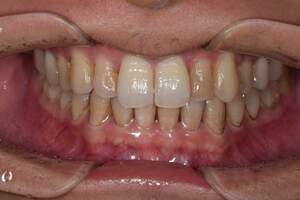

歯石除去・オフィスホワイトニング

治療前

治療後

| 年齢 | 30歳・女性 |

| 主訴 | クリーニング・歯を白くしたい |

| 治療内容 | 歯石除去・オフィスホワイトニング |

| 治療期間 | 60分×2回 |

| 費用 | 歯石除去 約2,000円 オフィスホワイトニング2回 6,600円(自費 診療) |

| リスク・副作用 | ・歯ぐきの炎症が強いと歯石を取る際に出血することがあります ・歯と歯の間に隙間ができるので、息が漏れ発音しにくいと感じることがあります ・歯ぐきの炎症が軽減すると歯ぐきが引き締まり、歯が長く見えることがあります ・ホワイトニングの効果は永久的なものではなく徐々に色戻りが起こります ・ホワイトニング後は歯の表面の水分量が一時的に少なくなりしみることがあります ・ホワイトニングは自費診療の施術です |